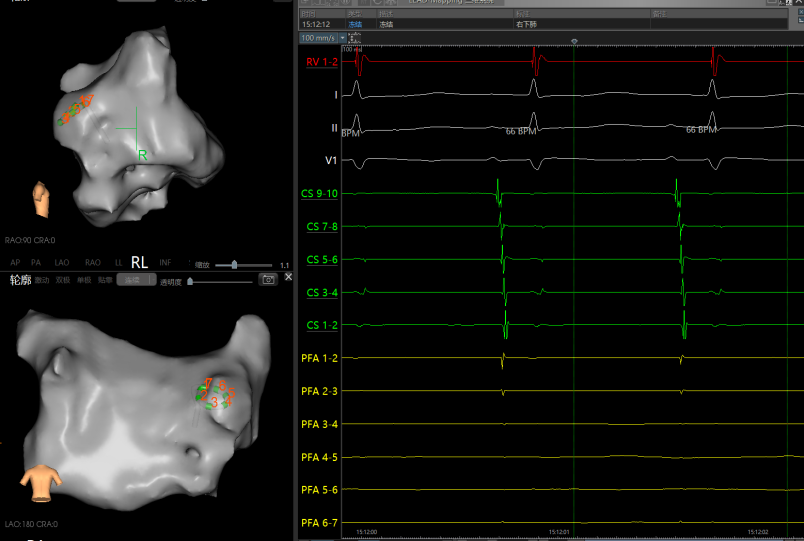

消融后左/右侧肺静脉电位

房扑再次发作:观察中再发房扑,周长为260-280,且CS顺序发生变化,遂重新进行激动标测。

激动从后壁沿着底部和左侧向前壁激动,形成顶部依赖的大折返。

顶部依赖折返激动图